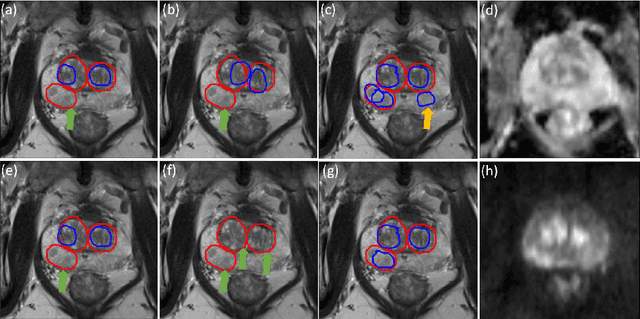

Prostate cancer (PCa) is one of the leading causes of death for men worldwide. Multi-parametric magnetic resonance (mpMR) imaging has emerged as a non-invasive diagnostic tool for detecting and localising prostate tumours by specialised radiologists. These radiological examinations, for example, for differentiating malignant lesions from benign prostatic hyperplasia in transition zones and for defining the boundaries of clinically significant cancer, remain challenging and highly skill-and-experience-dependent. We first investigate experimental results in developing object detection neural networks that are trained to predict the radiological assessment, using these high-variance labels. We further argue that such a computer-assisted diagnosis (CAD) system needs to have the ability to control the false-positive rate (FPR) or false-negative rate (FNR), in order to be usefully deployed in a clinical workflow, informing clinical decisions without further human intervention. This work proposes a novel PCa detection network that incorporates a lesion-level cost-sensitive loss and an additional slice-level loss based on a lesion-to-slice mapping function, to manage the lesion- and slice-level costs, respectively. Our experiments based on 290 clinical patients concludes that 1) The lesion-level FNR was effectively reduced from 0.19 to 0.10 and the lesion-level FPR was reduced from 1.03 to 0.66 by changing the lesion-level cost; 2) The slice-level FNR was reduced from 0.19 to 0.00 by taking into account the slice-level cost; (3) Both lesion-level and slice-level FNRs were reduced with lower FP/FPR by changing the lesion-level or slice-level costs, compared with post-training threshold adjustment using networks without the proposed cost-aware training.